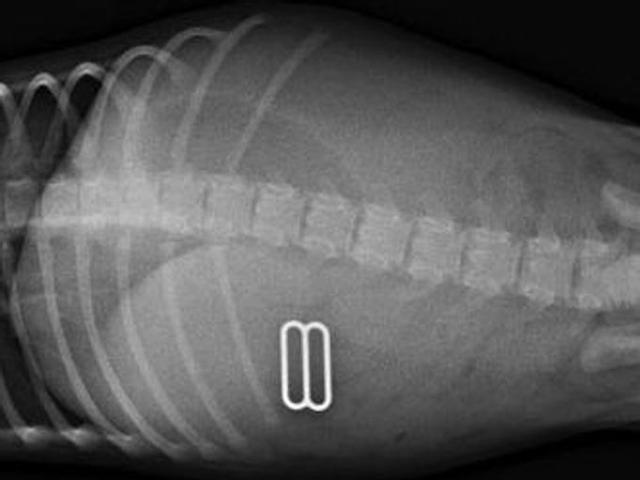

宠物作死大赛, 它们到底吃过什么东西, 医生用X光告诉你